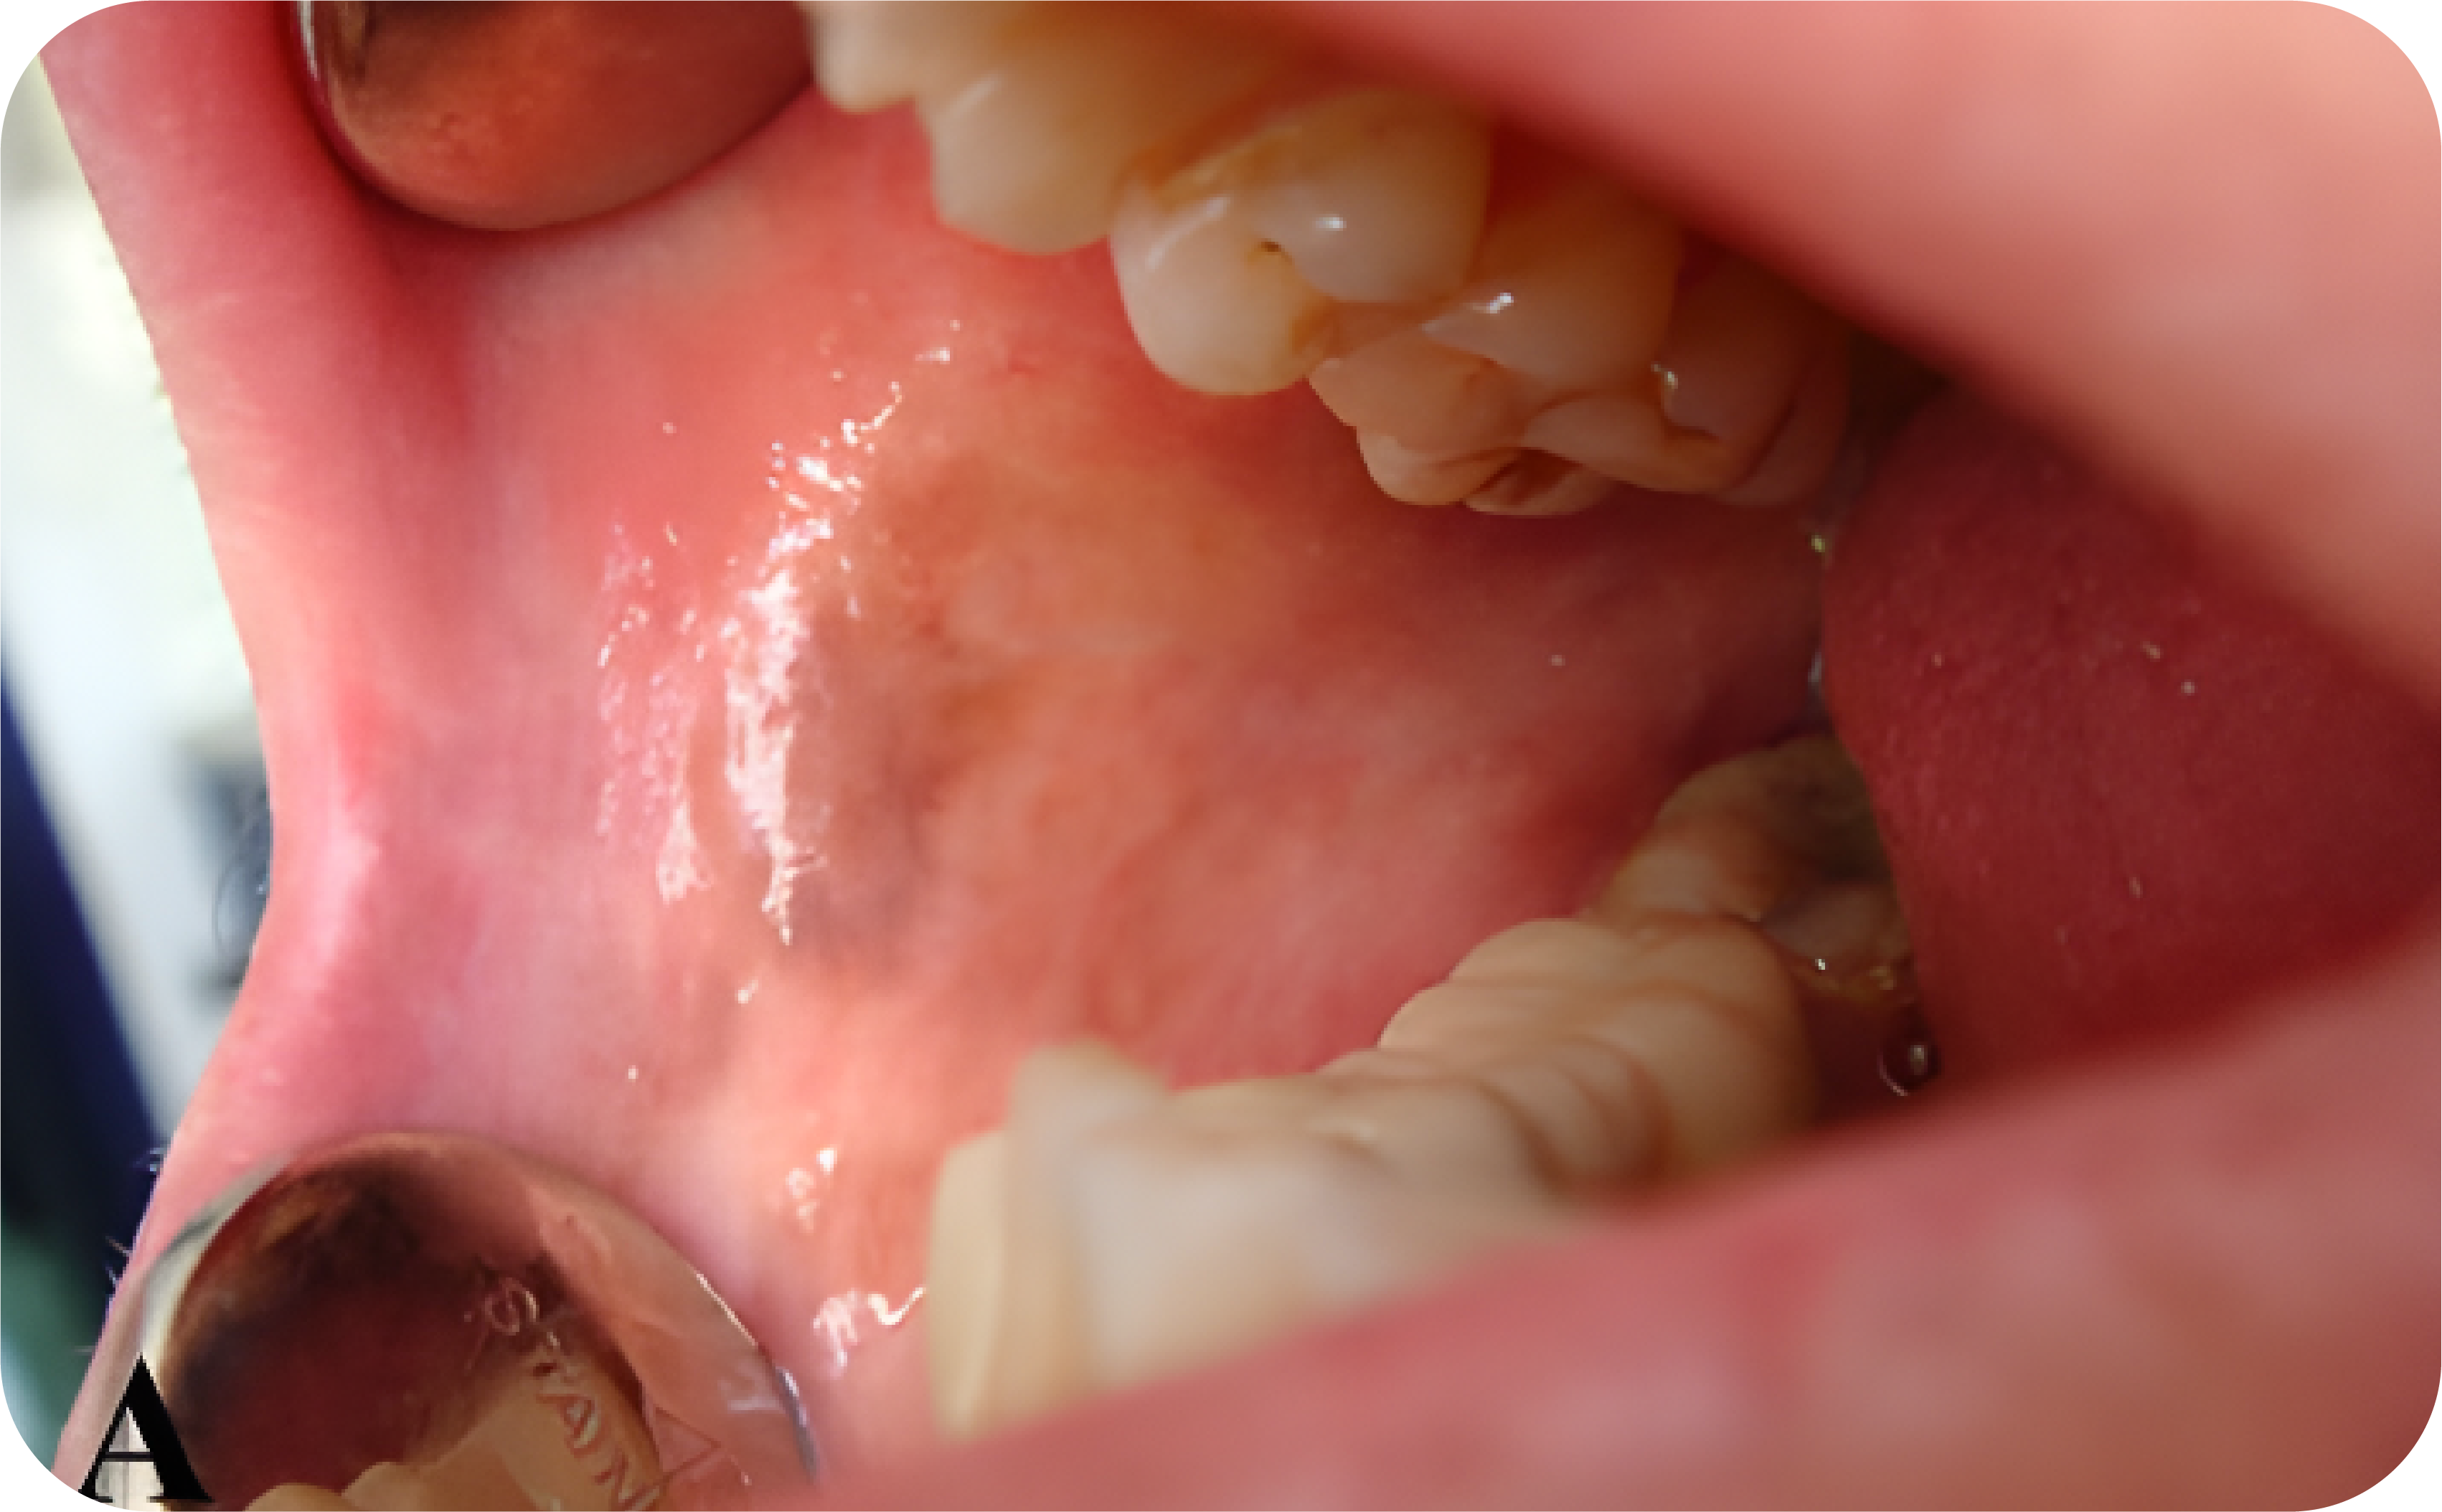

Adanya bercak berwarna coklat difus yang menyebar dengan diameter kurang dari 1 cm dan letaknya paling sering nampak di gingiva anterior mandibula dan mukosa bukal.